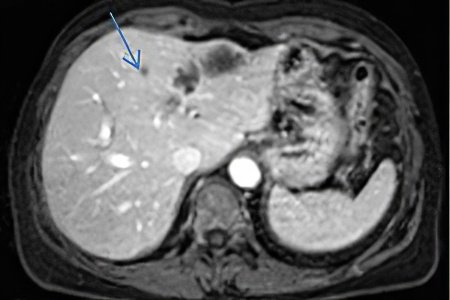

- Печень;

У 95% пациентов первичные отдалённые метастазы возникают в печени. В этом случае орган увеличивается в размерах и становится более плотным, что может вызывать дискомфорт и тяжесть в правом подреберье. С увеличением числа метастазов происходит замещение печёночной ткани, что нарушает её функции и может приводить к желтушности кожи.